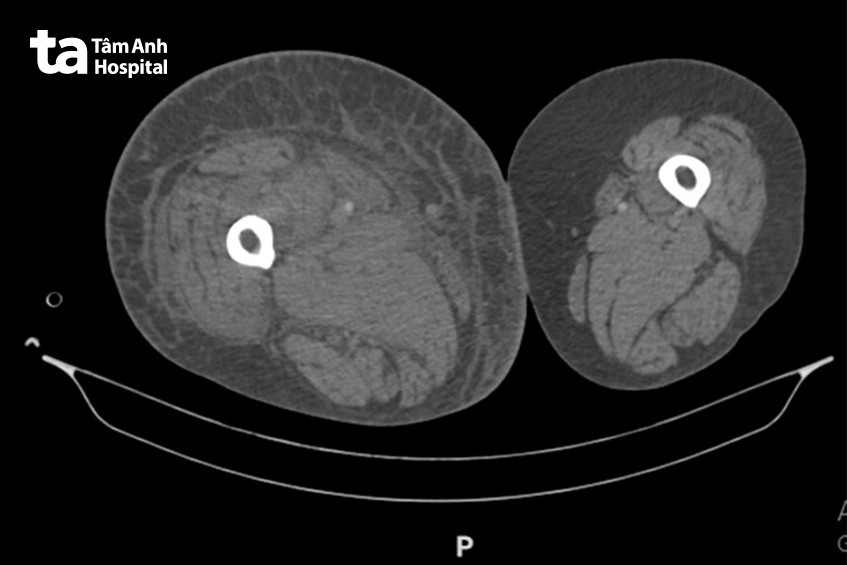

BS.CKII Nguyễn Thu Trang, khoa Tim mạch, cho biết, qua thăm khám lâm sàng kết hợp các kỹ thuật chẩn đoán như siêu âm mạch máu chi dưới, chụp cắt lớp vi tính mạch máu, bác sĩ phát hiện bà Hoa có huyết khối lấp gần như hoàn toàn hệ tĩnh mạch sâu chi dưới phải, huyết khối lan đến tầng chậu đùi, ngoài ra người bệnh đã biến chứng thuyên tắc phổi – dấu hiệu cho thấy một phần huyết khối đã di chuyển từ chân lên phổi theo dòng máu.

Trường hợp nặng như bà Hoa, huyết khối chèn gần như toàn bộ hệ tĩnh mạch, lên đến tầng chậu đùi, khiến chân phải sưng to gấp đôi, đau nhức và gần như không thể vận động. Nguy hiểm hơn, nếu huyết khối không được xử trí kịp thời, các mảnh nhỏ có thể tiếp tục bong ra và di chuyển đến phổi, gây thuyên tắc phổi mức độ nặng, có thể dẫn tới suy hô hấp và tử vong.